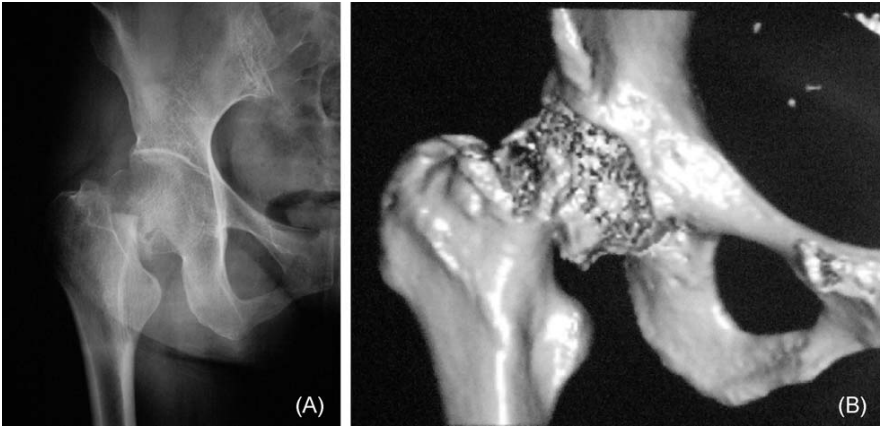

或者,更罕见的是,近端节段旋转后嵌插入远端部分,并作为一个整体随远端部分移动。结果,移位-嵌插型股骨颈骨折无法通过手法操作复位(图2)。

图 2. 一名54岁女性从约1.5米高处坠落导致的难复性右股骨颈骨折。远端节段嵌插入近端部分并随之旋转,脱位的股骨头无法通过手法操作复位(A,前后位X光片;B,右股骨颈骨折的CT三维重建图像)。